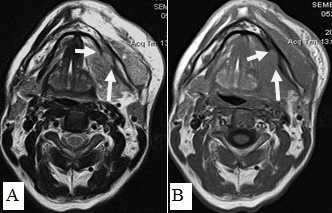

Рис. 10. А. Пациент Е., 52 года. МРТ полости рта, ротоглотки в аксиальной проекции, Т1-ВИ. Опухоль языка небольших размеров, границы визуализируются с трудом за счет перифокального отека (стрелки); В. Тот же пациент. МРТ в аксиальной проекции, Т2 с подавлением сигнала от жировой ткани. Визуализируются границы опухолевого узла, размеры опухоли языка четко определяются (стрелки)